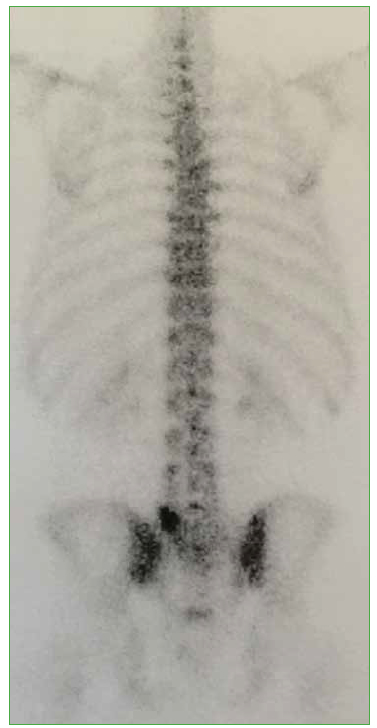

8. Crawford BA, van der Wall H. Bone scintigraphy in acute intraosseous disc herniation. Clin Nucl Med 2007;32:790-2. https://doi.org/10.1097/RLU.0b013e318149ee54